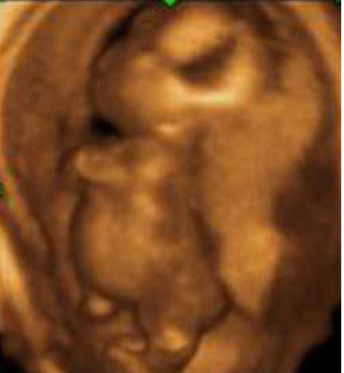

Pena-Shokeir Syndrome - Knees hyperextended, arms contracted and crossed over, Polyhydramnios, Micrognathia,